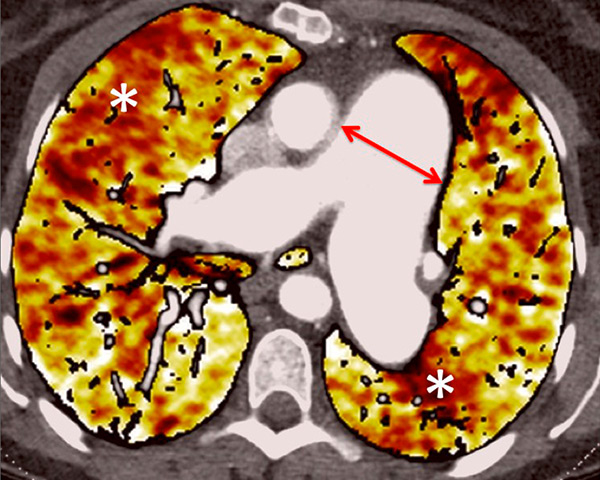

Figure 7

Portopulmonary hypertension in a 16-year-old. No abnormalities were found on morphological computed tomography (A/B), but heterogeneous perfusions were present on the perfusion map (stars, C/D).